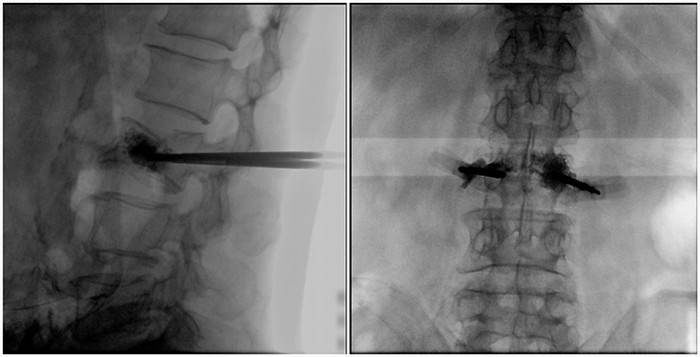

普愛醫(yī)療大平板一體式移動C臂采用30cm×30cm的平板探測器,能在手術(shù)過程中,為醫(yī)生提供更廣闊的視野范圍,帶給醫(yī)生更全面的影像信息。在進行脊柱類手術(shù)時,一次曝光即可呈現(xiàn)全節(jié)段腰椎,避免因為呈像不全而導(dǎo)致重復(fù)曝光,不僅提高了手術(shù)效率,而且避免醫(yī)生吸收過量的輻射。